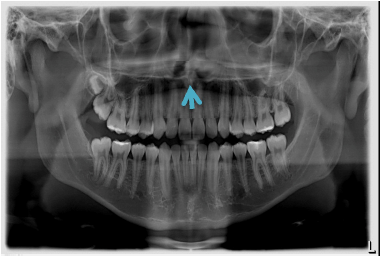

Sobre a anatomia radiográfica, identifique a seguinte estrutura:

Provas